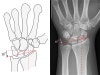

4. Radiocarpal angle

1) Measured by first establishing reference lines. These are the radial centreline and a right-angle line.

2) Formed between this right angle lien and a line drawn from the tip of the radial styloid to the tip of the ulnar styloid.